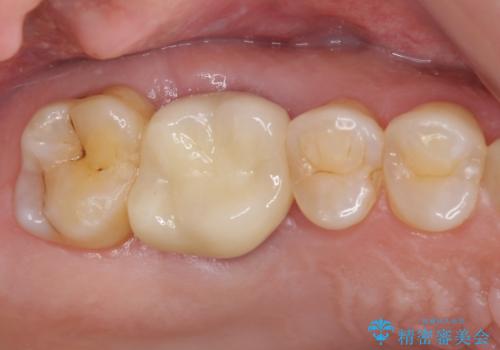

不適合なクラウンのやりかえ

セラミッククラウンによる奥歯のむし歯治療